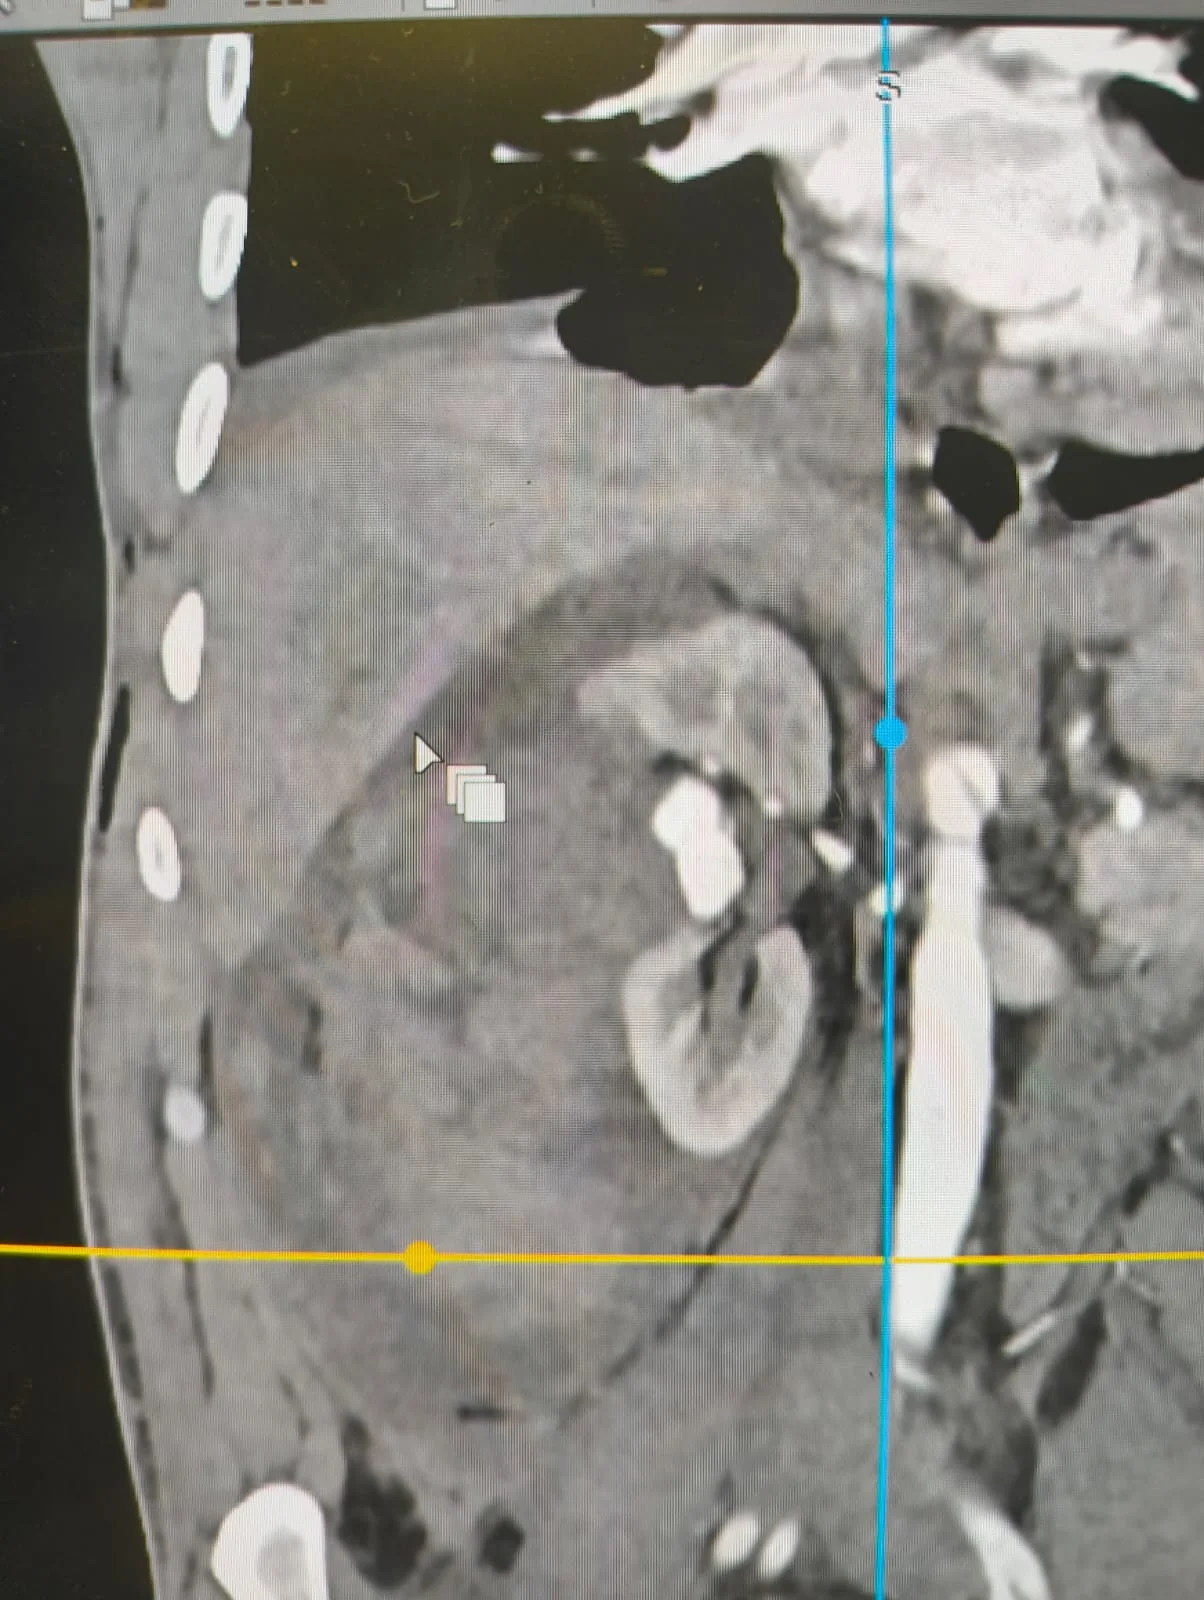

استمرارًا لمسيرة النجاح التى يحققها مستشفى كفر الشيخ الجامعى فى تقديم خدمات طبية متقدمة، نجح الفريق الطبى بوحدة الأشعة التداخلية تحت إشراف الدكتور محمود غلابمدير وحدة الأشعة التداخلية و استشارى الأشعة التداخلية، و زميل الأشعة التداخلية بجامعة هيروشيما، و مدرس الأشعة التداخلية بجامعة كفر الشيخ – فى إنقاذ حياة شاب تعرّض لحادث أدى إلى قطع جزئى فى الشريان الكلوى الأيمن مصحوبًا بتجمع دموى، و ذلك دون اللجوء إلى استئصال الكُلى.

تمكّن فريق الأشعة التداخلية بجامعة كفر الشيخ بقيادة د. محمود غلاب من إجراء تدخل طارئ ناجح تم خلاله سدّ التمدد الشريانى مع الحفاظ الكامل على التغذية الدموية لباقى أنسجة الكُلى، و هو ما يُعد من أبرز و أهم مميزات الأشعة التداخلية التى تهدف إلى إنقاذ العضو المصاب دون جراحة مفتوحة، و بأعلى درجات الدقة مع تقليل المضاعفات و فترة التعافى.

و تتميّز الأشعة التداخلية بقدرتها الفائقة على الوصول إلى أدق شرايين الجسم وإجراء تدخلات عالية الدقة و الصعوبة دون أى تدخل جراحى، و غالبًا دون الحاجة إلى التخدير الكلى فى كثير من الحالات، ما يساهم فى تقليل المخاطر و المضاعفات و تسريع تعافى المرضى مقارنة بالجراحات التقليدية.